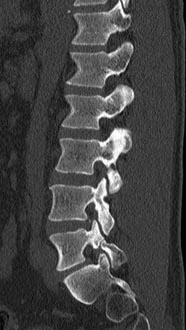

44 year old man with severe low back pain with intermittent radiation of the pain down the right leg. After undergoing conservative treatment, continued to have debilitating pain. MRI revealed a right paracentral disc herniation but CT scan revealed a unilateral pars fracture. After debating on microdiscectomy vs fusion, patient elected to undergo lumbar fusion. 4 months postop patient returned to surfing again. 9 months postop patient wrote “My recovery continues to do very well and we just got back from 8 days camping which including mountain biking, hiking, and a lot of work. Surfing almost every day and life is good…you have helped get my life and my families life back to normal.”

After procedure.